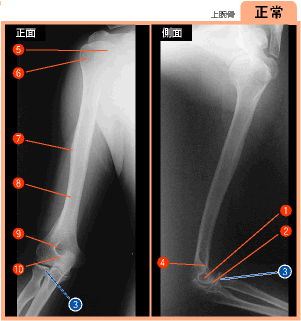

▲258ページ 正常画像内(2007/2/5)

※正面:3の引き出し線を追加,側面:3の引き出し線を修正(下は修正済みの画像です.青い線で示しています)

| ● |

|